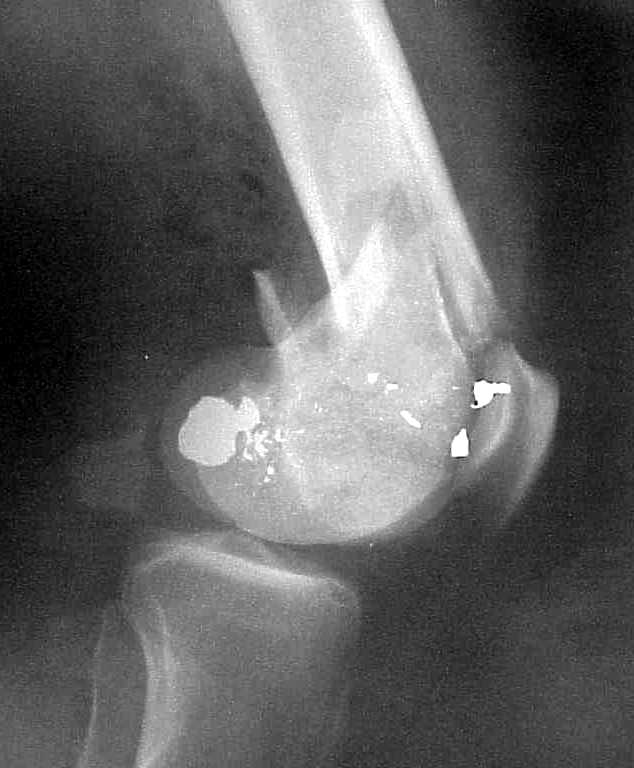

of course the only radiograms both the view of the femur (AP and LL) are not enough in order to assess the condilar ones.

So I think a TAC of the knee could be useful.

A CT and knee xrays would help identify lateral condyle comminution and/or a "hoffa fragment" of the posterior condyle. I am concerned that the lateral cortex is not sufficient to give purchase for a retrograde IMN. blocking screws could improve this as a possibility. A long blade or LISS if avaible would be my secondary choices. Good luck. Any chance you can get these cases transferred earlier when it

Lateral condyle looks too small for the blade, and the plate too short.